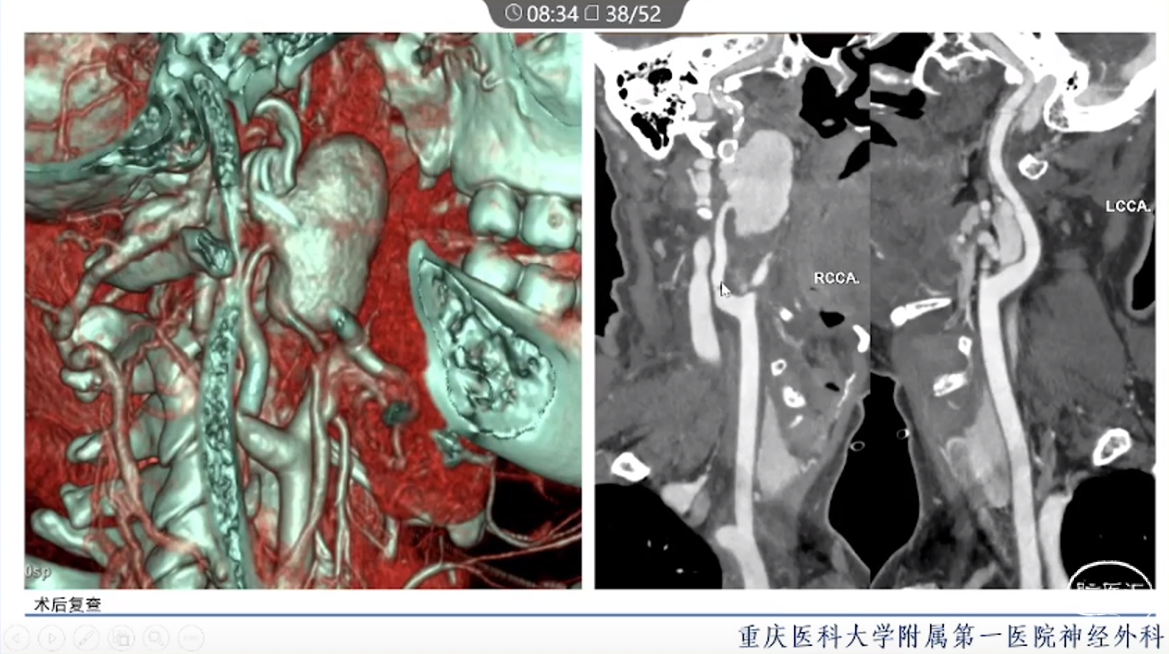

·颈内动脉颈段动脉瘤治疗方式有血管内治疗、外科手术和保守治疗。

·血管内治疗是最常见的治疗方式,随着血管内介入技术的发展和材料的进步,越来越多的动脉瘤可以通过血管内途径治疗。

·对于血管扭曲、血管直径大以及存在抗血小板禁忌的动脉瘤患者,特别是对于颈段大型或巨大型动脉瘤的治疗,常需要外科手术治疗。